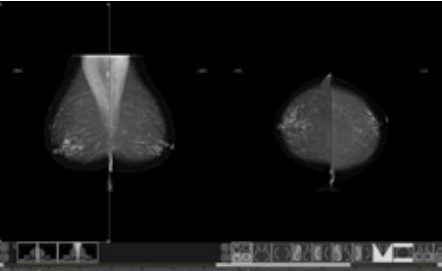

乳腺科AI辅助诊断:支持跨厂牌调阅乳房摄影影像。可呈现V型屏蔽、中央屏蔽、CAD Mark、PR;可在同个工作站整合Mammo、US、MR、NM影像;并可自定义多种挂片模式及一键看片流程。